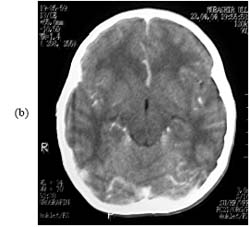

Các kháng thể đặc hiệu với Angiostrongylus cantonensis có thể phát hiện trong huyết thanh và trong dịch não tủy trên 25% số bệnh nhân. Mặc dù chẩn đoán các liên quan đến hệ thần kinh đã được thiết lập trên lâm sàng, các phương pháp xét nghiệm huyết thanh học như ELISA, nơi mà sẵn có các bộ thử - có thể giúp cho việc củng cố chẩn đoán. Đôi khi, ấu trùng đang sống có thể phát hiện trên kính hiển vi thông qua xét nghiệm dịch não tủy, sinh thiết mắt và các mô khác. CT scan não có thể bình thường hoặc có thể biểu hiện các hình ảnh không đặc hiệu, gồm phù não, dãn não thất hoặc tăng vòng tổn thương. Tương tự, chụp cộng hưởng từ (MRI) có thể cho các hình ảnh không đặc hiệu từ bình thường đến viêm màng não tủy mềm leptomeningeal tăng sinh, phì đại não thất (ventriculomegaly), tăng nhiều vùng có đốm nhỏ bát thường ở hạch nền. Điều này liên quan đến độ trầm trọng của nhức đầu, xuất hiện giun trong dịch não tủy, tăng lympho bào và bạch cầu ái toan trong dịch não tủy và cả máu ngoại vi. Bệnh ung thư bạch cầu thể tăng bạch cầu eosin nên loại trừ nhờ vào xét nghiệm tủy xương. Một tỷ lệ bất thường giữa các tế bào tiền tủy của bạch cấu ái toan (eosinophilic promyelocytes) với bạch cấu ái toan phân đoạn (segmented eosinophils) là hữu ích cho chúng ta trong việc phân biệt giữa ca bệnh ung thư bạch cầu dòng bạch cấu ái toan (eosinophilic leukemia) và tăng bạch cầu eosin phản ứng (reactive eosinophilia). Đến 30% số bênh nhân bị viêm màng não do nấm coccidioid có thể có kết quả xét nghiệm dịch não tủy gần giống như của EM. Một số chẩn đoán phân biệt khác gồm u lymphoma, hội chứng tăng nhiễm bạch cầu eosin, dùng thuốc ibuprofen và ung thư bạch cầu nguyên bào lympho cấp. Các nguyên nhân khác thường gặp và hiếm gặp theo bảng 1.